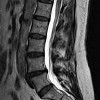

МРТ-миелография позвоночника

Магнитно-резонансная миелография. Современное исследование путей спинномозговой жидкости, включающее введение особого контраста в субарахноидальное пространство и использование ядерно-магнитно-резонансной томографии для создания серии томографических изображений. Обеспечивает качественную визуализацию образований мягких тканей исследуемого позвоночника, позволяет оценить структуру позвоночного канала, выявить выпячивания, вырезы и области сдавления спинного мозга. Это делается после введения контраста. Он проводится во время первичной или дифференциальной диагностики рака, инфекционных и воспалительных процессов, травматических поражений, стеноза позвоночного канала, нарушений кровообращения, пороков развития, межпозвонковой грыжи, сирингомиелии и других патологий.